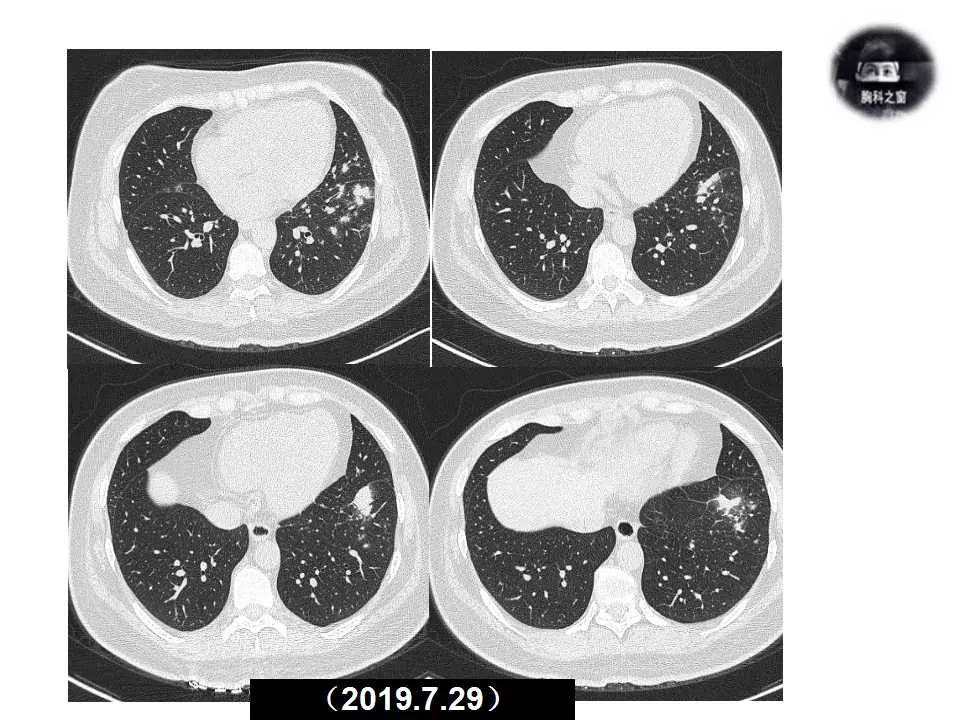

主诉:发现左肺病变1天

现病史:患者1天前体检胸部CT提示左肺病变,之前一段时间进食较少,七月初、七月中旬出现咳嗽、胸痛、无法深呼吸,无咯血,无乏力、盗汗,无明显体重减轻,为接受进一步诊治收入院。(2019.7.30)

影像诊断:真菌性肺炎,隐球菌可能性大。

追问病史,有近距离接触鸽子史。隐球菌抗原(+)。

肺隐球菌病